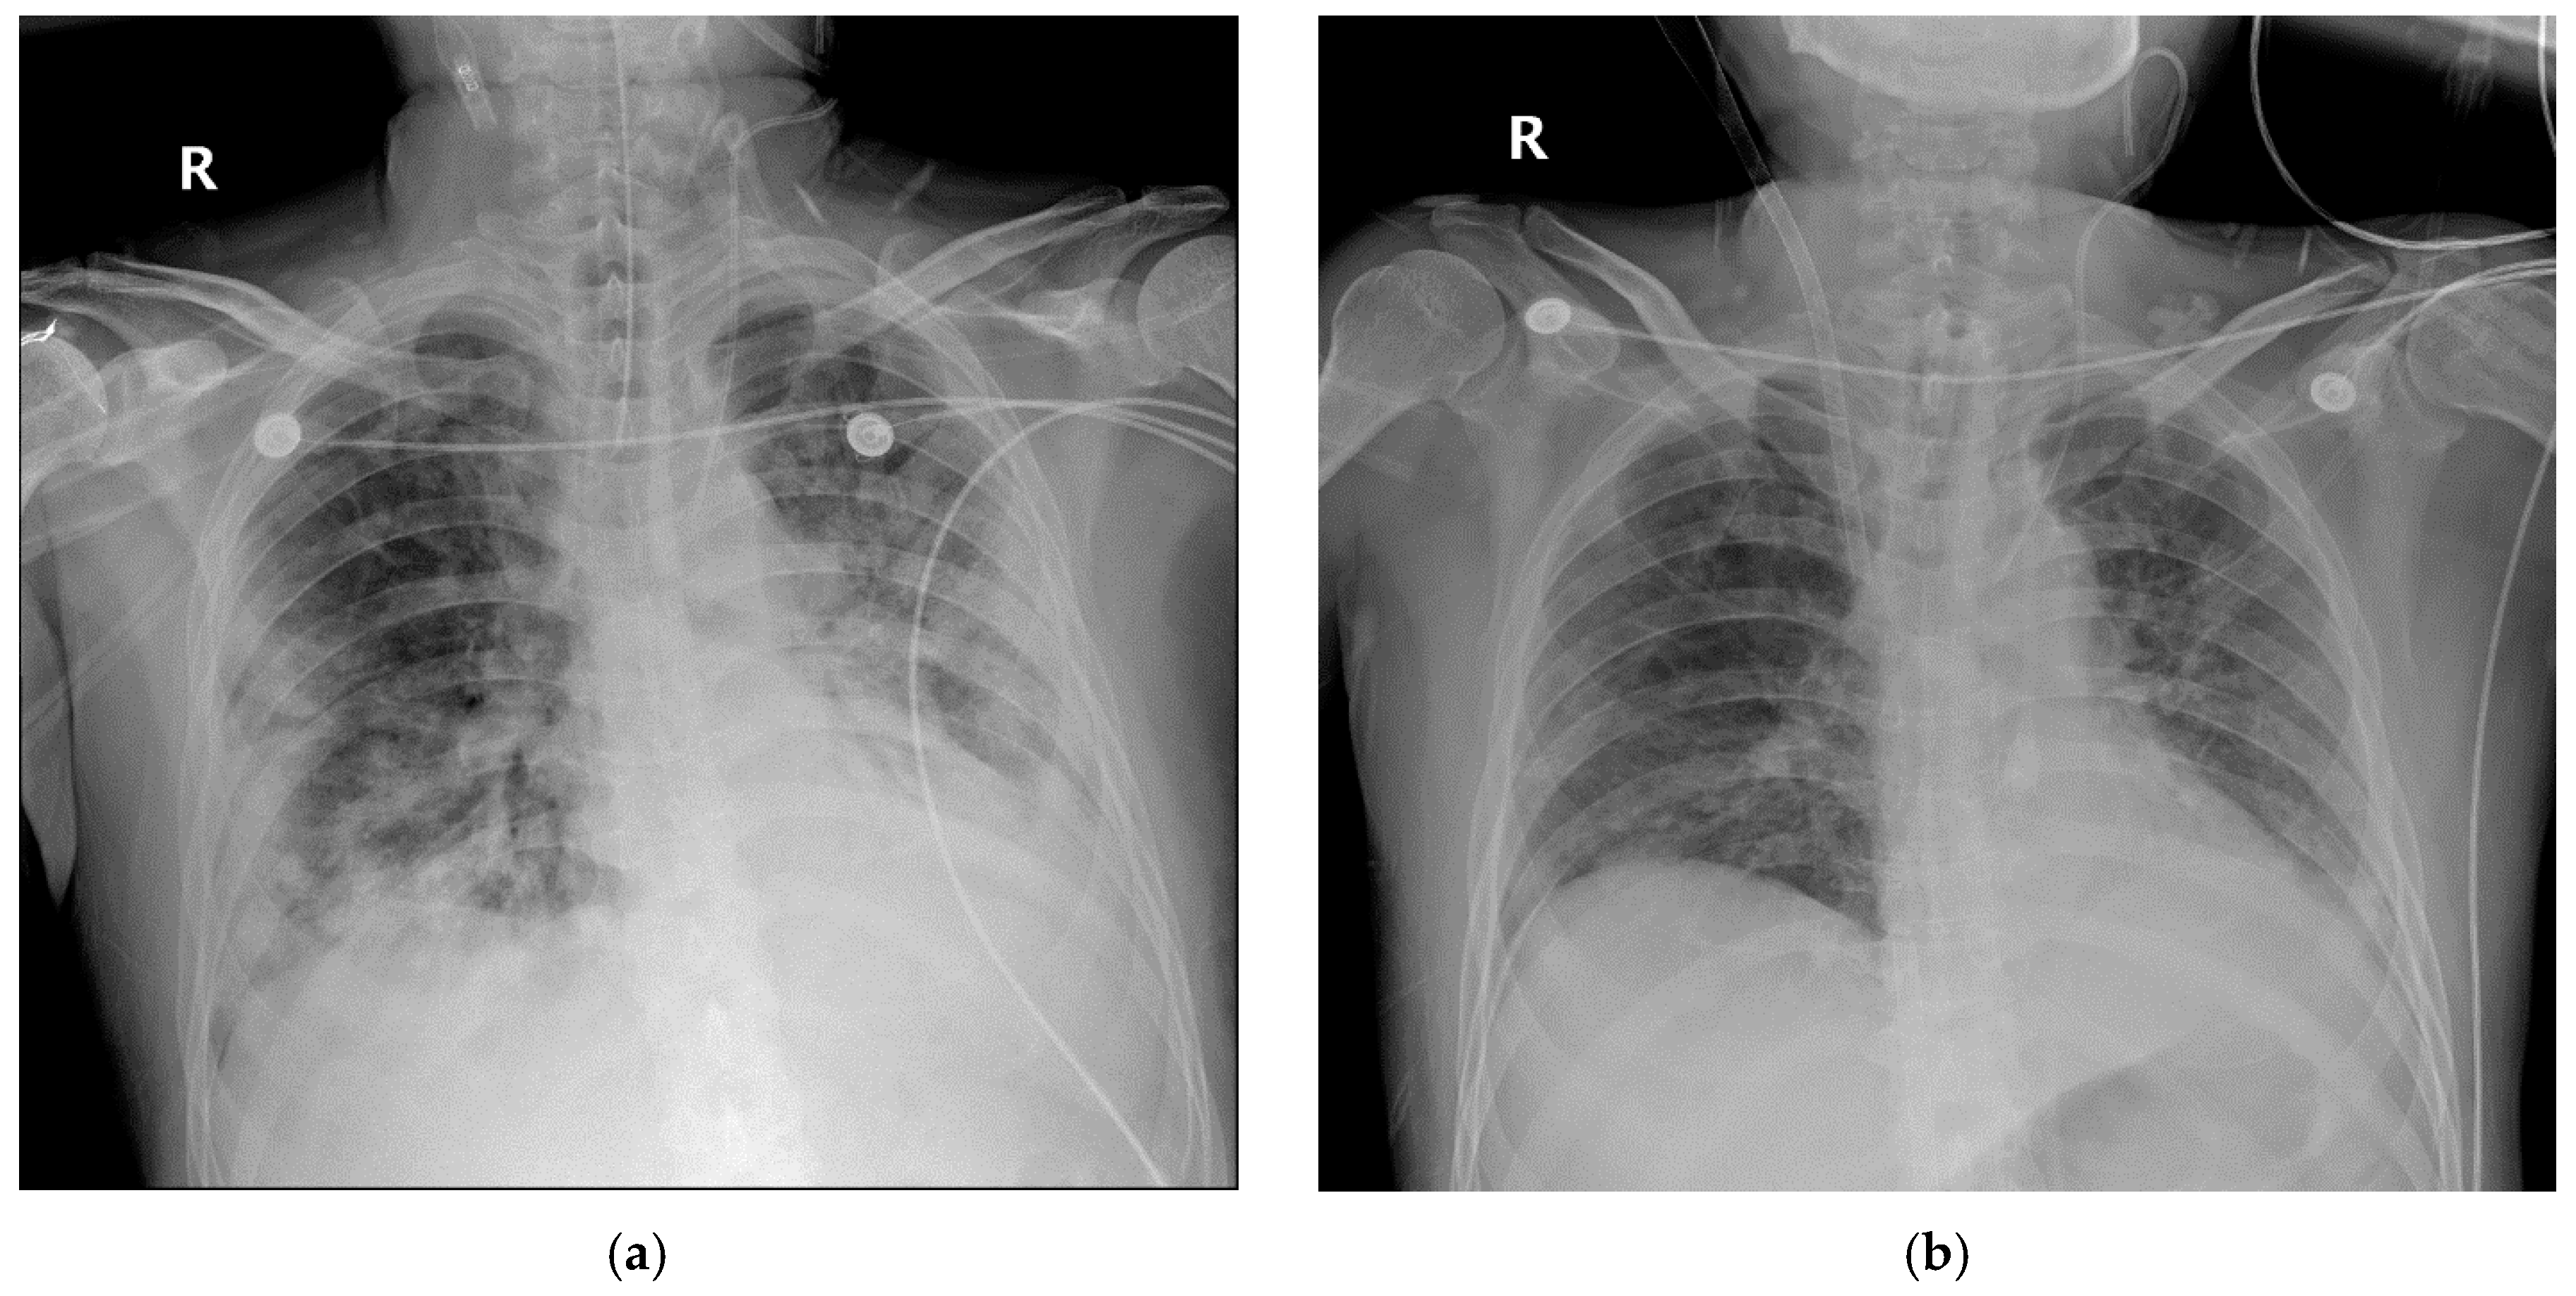

2.1. Case 1

2.2. Case 2

2.3. Case 3